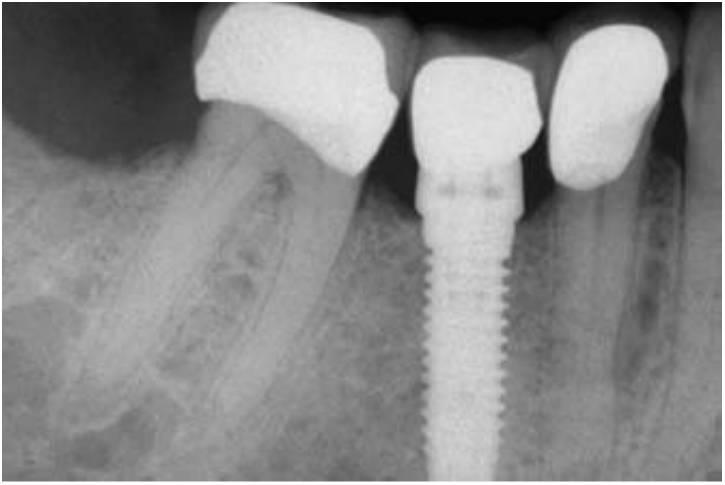

Un tratamiento opcional para sustituir a un solo diente perdido es un implante dental unitario (fig. 1-8). Durante años, los pacientes debían aparcar sus deseos y aceptar las limitaciones de una PPF. Sin embargo, muchos sienten que el método más natural de reemplazar un diente es emplean do un implante, más que preparando los dientes adyacentes y uniéndolos con una prótesis. Los motivos principales para sugerir el uso de las PPF fueron su facilidad clínica y su reducido tiempo de tratamiento. En cualquier caso, si se expandiera este concepto, las extracciones reemplazarían a las endodoncias y las dentaduras podrían incluso reemplazar a las ortodoncias. El motivo principal para sugerir o llevar a cabo un tratamiento no debería tener relación con el tiempo de tratamiento o la dificultad del procedimiento, sino que debería ser la mejor solución posible a largo plazo para cada individuo.

Desde 1993 hasta la fecha, los estudios sobre la supervivencia de los implantes individuales han validado este procedimiento como el método de sustitución dental más predecible. En la literatura existen más publicaciones sobre el implante dental unitario que sobre cualquier otro método de sustitución dental35'47, y todos los estudios mostraron una media de supervivencia más alta en los implantes den tales individuales. Goodacre y cols, publicaron una revista literaria médica desde 1980 hasta 2001 y observaron que la media de éxito del implante dental unitario era hasta del 97% , más alta que cualquier otra restauración implantológica. En 1995, Haas y cols, estudiaron 76 implantes den tales unitarios sobre un período de 6 años y observaron una media de supervivencia del 97% y un 2 % de pérdida del implante. Fugazzotto evaluó 1.472 implantes en un período de 13 años y observó una media de supervivencia del 97 % durante ese período.

Aunque la sustitución dental posterior individual es un tratamiento alternativo relativamente reciente, se han publicado numerosos estudios desde 1990, y las medias de supervivencia referidas van desde el 9 4 ,6 % hasta el 100% sobre períodos que van desde 1 año hasta 15 años. En estos estudios la media de pérdida del implante es del 2,8% sobre un período de 5 años. En comparación, la media de fracaso en las PPF es del 2 0 % sobre 3 años, y se pueden esperar fracasos del 50 % sobre períodos de 10 años. como resultado, el implante dental unitario exhibe la mayor media de supervivencia entre las sustituciones dentales individuales. Y tan importante es que ningún estudio refiere la pérdida de un diente adyacente, lo que es una ventaja considerable. Por otra parte, no se ha determinado de manera adecuada la longevidad de la pieza o corona implantaría al no extenderse tanto estos estudios como los de otras opciones de tratamiento.

Salvo algunas limitaciones y desafíos clínicos evidentes, el implante dental unitario representa un tratamiento de elección desde el doble punto de vista de la salud y el valor. Cuando los dientes adyacentes están sanos, o el paciente rechaza su preparación para la fabricación de una unidad tradicional de restauración de tres unidades, un implante dental posterior unitario es una solución excelente (fig. 1-9). Las ventajas relacionadas con la salud de esta modalidad respecto a la restauración fija parcial se enumeran en el cuadro 1-2 e incluyen disminución del riesgo de caries y de enfermedad periodontal, disminución del riesgo de pérdida de un pilar dental por caries o fracaso del tratamiento endodóncico y mejoría estética (fig. 1-10).